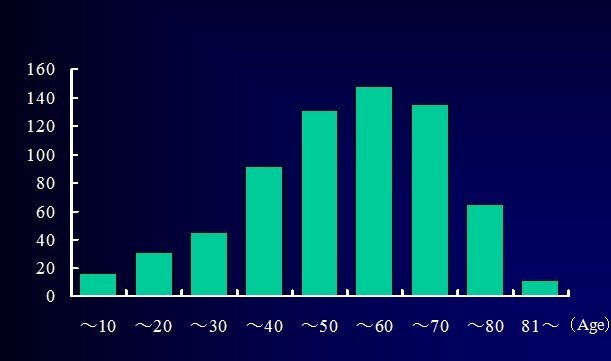

Hiroshi Ozawa等总结分析了674例椎管内肿瘤患者的病例特点: